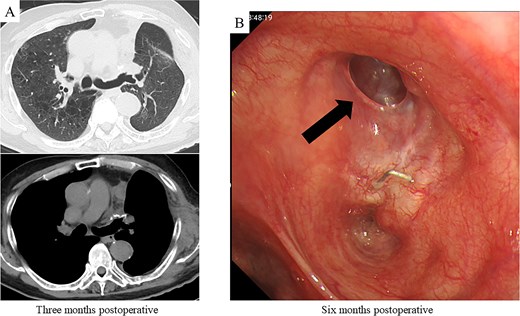

After harvesting the latissimus dorsi flap through a posterolateral incision, a thoracotomy was performed. Intrathoracic adhesions were dissected to expose the bronchial stump fistula, which measured ~10 mm (Fig. 2A); no evidence of empyema was observed. Given the large, deep configuration of the fistula, which would complicate delivery and complete coverage of the flap, a bronchoscope was inserted and biopsy forceps were advanced through the fistula into the thoracic cavity. The latissimus dorsi flap was grasped with the forceps, guided into the thoracic cavity, and secured in place with sutures (Fig. 2B). Fibrin glue was applied around the repair site for reinforcement (Fig. 2C). After confirming the absence of any air leak, the procedure was completed (Supplementary video 1). The operation lasted 140 min, with an estimated blood loss of 20 ml. The postoperative course was uneventful. On postoperative day 7, CT and bronchoscopy confirmed that the latissimus dorsi muscle had retrogradely filled the bronchial lumen and that the fistula was completely closed (Fig. 2D and E). The patient was discharged 13 days postoperatively, and home oxygen therapy was discontinued. Follow-up CT scans at 3 months showed gradual retraction of the latissimus dorsi muscle from the bronchial lumen, yet no residual air space was observed (Fig. 3A). At 6 months, bronchoscopy revealed satisfactory granulation tissue formation at the upper lobe bronchial stump, indicating complete healing (Fig. 3B).

Postoperative CT imaging and bronchoscopic evaluation. (A) CT scans at 3 months postoperatively reveal no recurrence of air leakage, indicating a stable clinical course. (B) Bronchoscopic examination at 6 months postoperatively shows satisfactory granulation tissue formation at the upper lobe bronchial stump, consistent with complete healing.